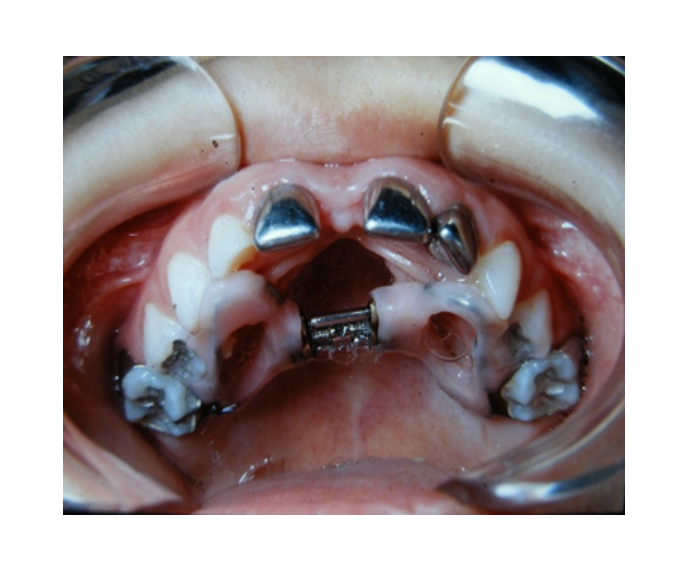

Chupadedos